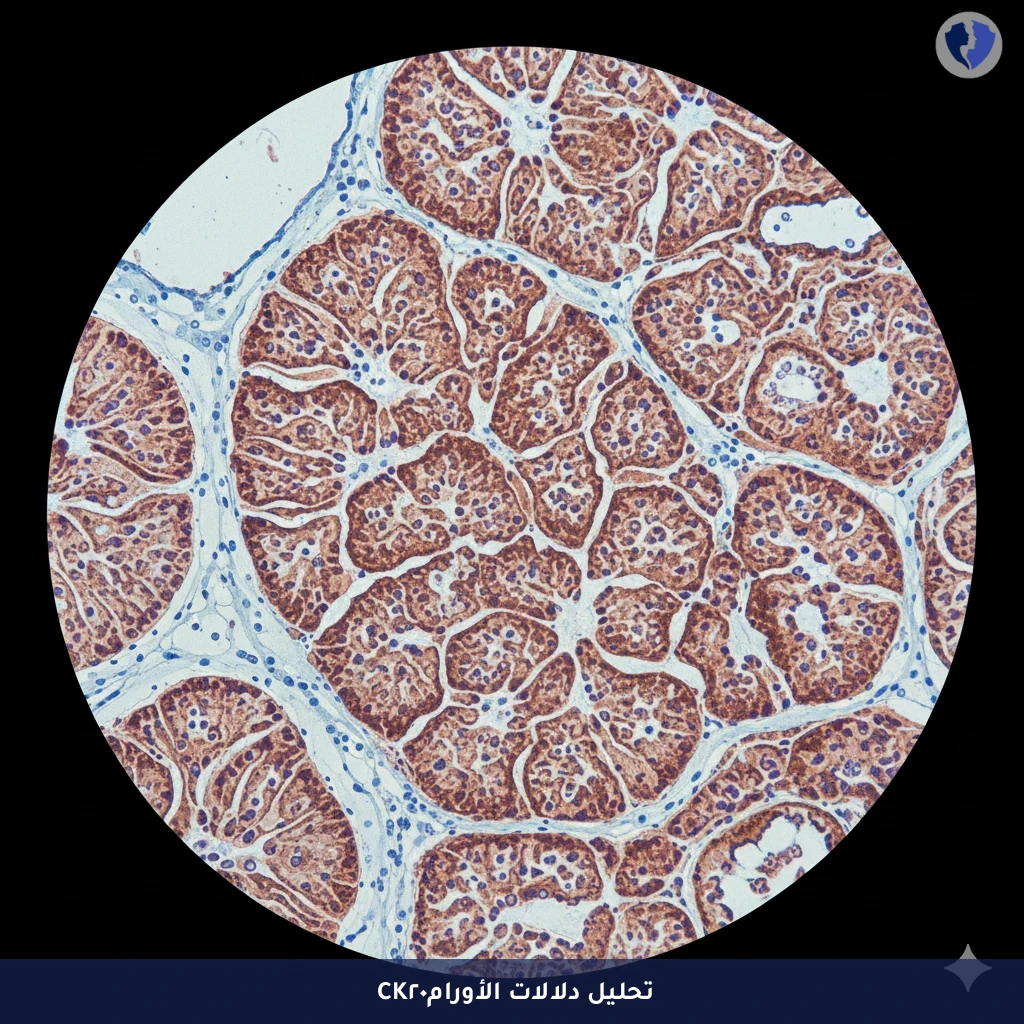

تحليل CK20 لأورام الهضم - فحص كيميائي نسيجي مناعي لسيتوكيراتين 20 (CK20)

الصورة التوضيحية المرتبطة بهذه الخدمة